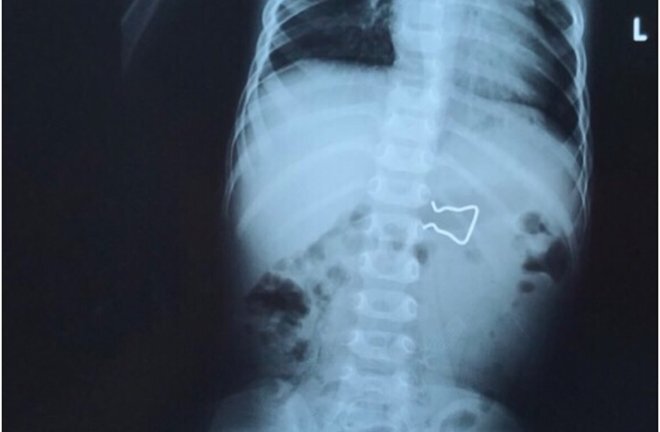

Một đoạn dây inox cong queo với nhiều cạnh sắc nằm gọn trong bụng bé trai 18 tháng tuổi được các bác sĩ Bệnh viện Nhi đồng 2 nội soi gắp ra thành công.